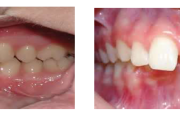

Esimese jäävmolaari ektoopiline lõikumine

Ravijärgne seis. Jäävhammas on täielikult lõikunud.

) Röntgenülesvõte. Ülemise esimese jäävmolaari lõikumine on takistatud 2. piimamolaari tõttu